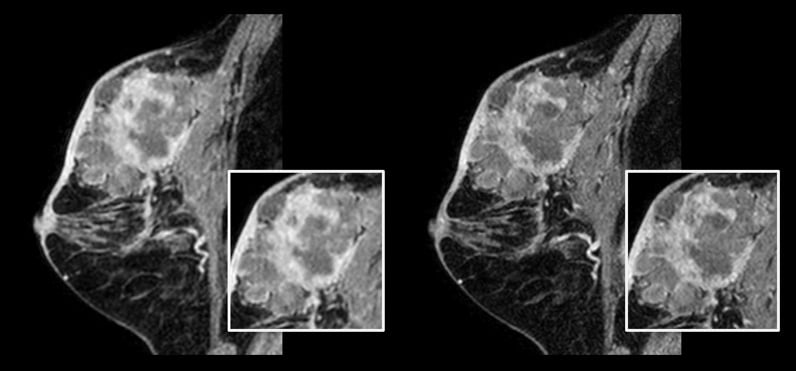

Paziente con cancro della mammella.

A sinistra: scansione in 3D mDIXON XD convenzionale con dimensione voxel isotropica di 1,0 mm e tempo di scansione di 2,22 minuti

A destra: scansione in 3D mDIXON XD mediante Compressed SENSE con dimensione voxel isotropica di 0,8 mm e tempo di scansione di 2,21 minuti.

Per gentile concessione del centro ospedaliero di Kurashiki, Okayama (Giappone)